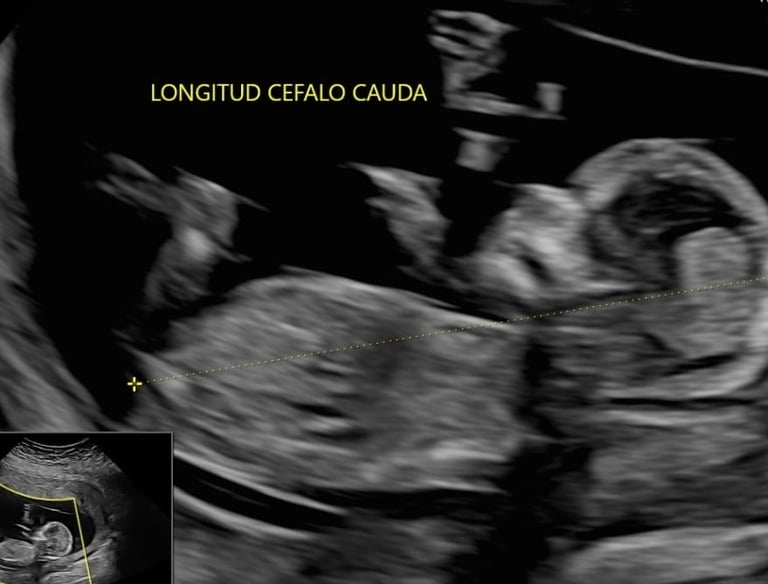

Tamizaje del Primer Trimestre, se realiza entre la semana 11 y 14.

Es la primera evaluación profunda de su salud, su formación y su bienestar.